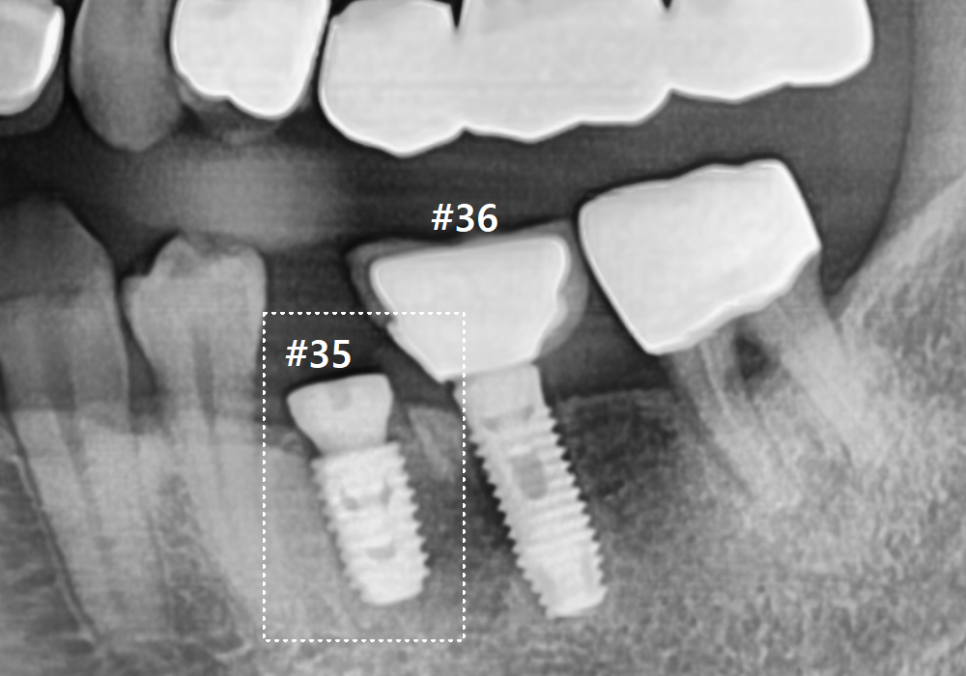

3개월 뒤,잇몸뼈가 단단하게

잘 아문 것을 확인하고

보철물 제작 단계로 들어갔어요.

이번에는 새로 심은 임플란트(#35)와

기존 임플란트(#36)를

하나로 튼튼하게 연결하는

스플린트(Splint) 방식을 선택했습니다.

두 개의 보철물을 각각 따로 만들지 않고

하나로 묶어주면,

치아 사이에 틈이 생기지 않아

음식물이 들어갈 자리를

원천적으로 차단할 수 있거든요.